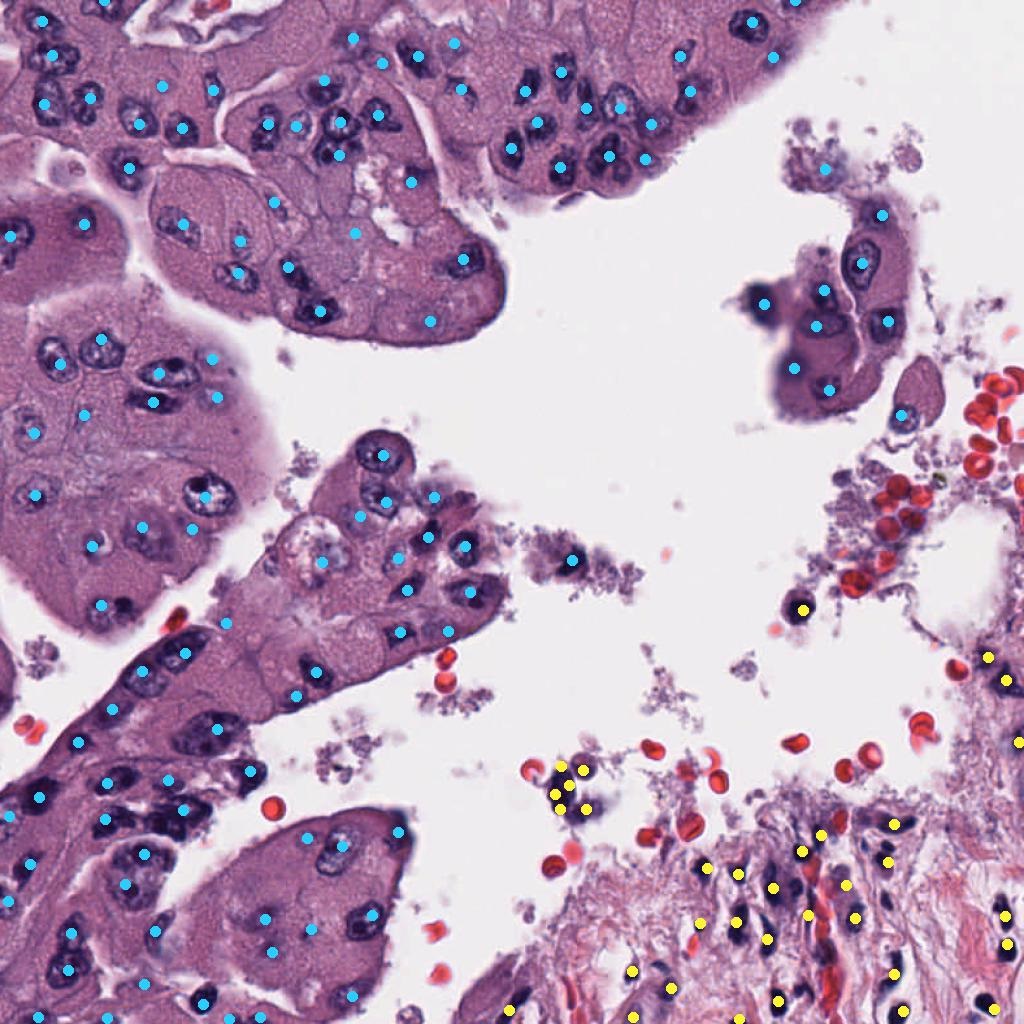

The sparse cell point annotations require translation into segmentation annotations. We investigate the following ground truth formats:

- 1.

-

2.

Hard instance segmentation (Hard IS): Inspired by [7] instance segmentation masks are derived from the image and centroid coordinates by applying NuClick222Publicly available at https://github.com/navidstuv/NuClick, last accessed 24.11.2023, a CNN-based segmentation model [1] that utilizes the centroid coordinates for nucleus instance segmentation (more details in Appendix 0.A). All pixels belonging to a nucleus instance are assigned the cells class label (Figure 2(b)). If the NuClick model was not able to segment a cells nucleus, we revert to the circle ground truth format.

-

3.

Soft instance segmentation (Soft IS): Motivated by [10], we place a Gaussian with (15 pixels at 0.2 mpp, different values are investigated in Appendix 0.C), centered at the centroid of each cell nuclei and set all background pixels not belonging to any NuClick cell instance to zero (Figure 2(c)). This results in a probability map for each class, where the background probability map is derived as the inverse of the combined cell probability maps .